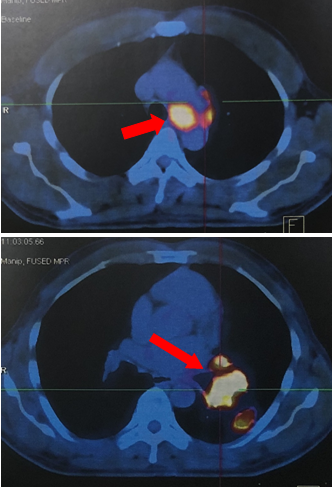

-Hình ảnh so sánh trước điều trị và sau điều trị 5 tháng.

Hình 4A: Trước điều trị: hình ảnh u phổi trái kích thước 4,6x4,3cm. Nốt tổn thương thứ phát phổi phải với kích thước 0,7cm (mũi tên đỏ)

Hình 4B: Sau điều trị 5 tháng: khối u thùy dưới phổi trái với kích thước 1,8x1,5cm (mũi tên vàng). Không thấy nốt tổn thương thứ phát phổi phải.

Hình 4C: Trước điều trị: hạch rốn phổi trải 1,9cm; Hạch trung thất trái 2,8cm (mũi tên đỏ).

Hình 4D: Sau điều trị 5 tháng: Không thấy hạch trung thất và không thấy hạch rốn phổi.